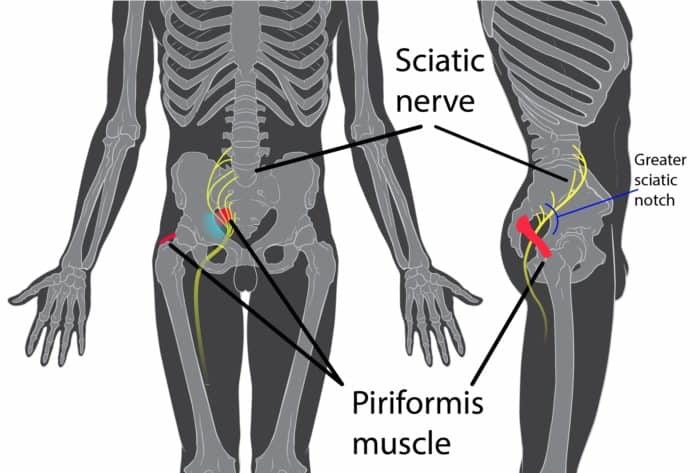

Piriformis Syndrome

The piriformis muscle is a flat, band-like stabilizer muscle that is deep within your buttocks. It assists in hip rotation, pelvic stability, and maintaining level hips while running.

If the piriformis is too tight or spasms from overuse, it may impinge on your sciatic nerve causing pain that will be felt in your rear and can radiate both into the lower back and down the leg.

There are certain risk factors that could predispose you to this condition:

- Sitting for long periods; extended periods of sitting can cause compression of the sciatic nerve

- Overuse; repetitive movements like running, walking, and cycling can cause inflammation, spasm, and hypertrophy of the piriformis, increasing the chances of sciatic irritation

- Trauma; injury to the gluteal area that causes swelling may lead to impingement of the sciatic nerve